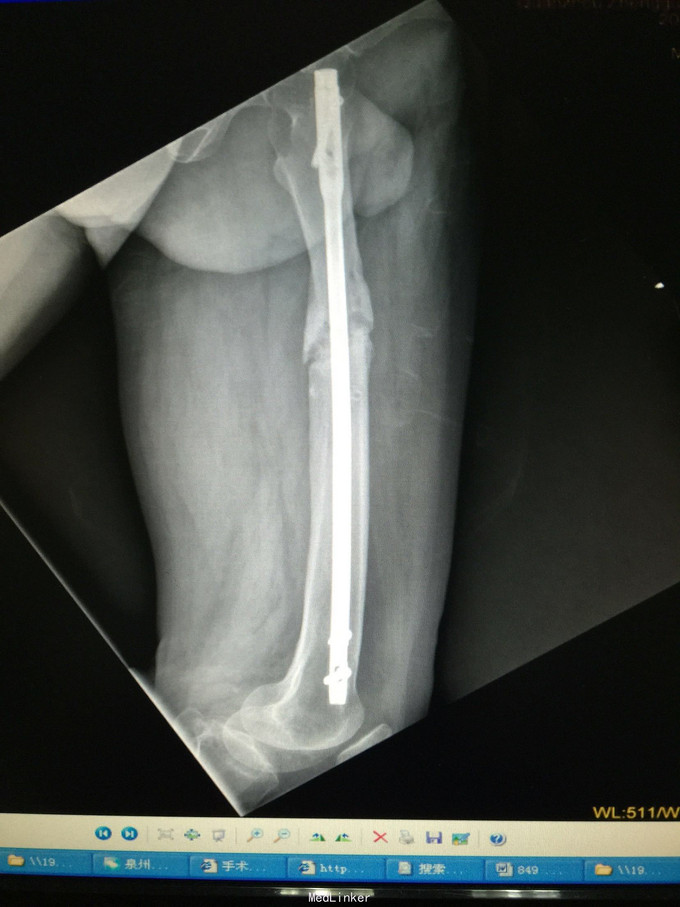

诊断:左股骨中上段骨折术后骨不连 处理:左股骨骨折术后骨不连断端清理+防旋钢板内固定+取髂骨植骨术

术后半年 讨论 考虑股骨中上段骨折 应力集中 近段一枚螺钉稳定性不够?